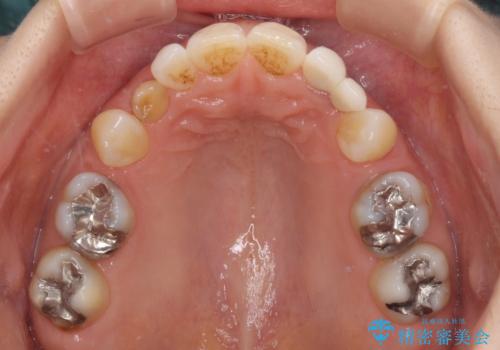

- 残存している乳歯や欠損部の隙間を気にして来院された患者様です。

上顎は左右ともに小臼歯が欠損しており、右側は乳前歯が残っている状態でした。

ブリッジによる補綴治療にて、欠損や隙間を補完することとしましたが、神経を取り除いたり、審美的に不自然になることを避けるため、部分矯正を併用することとしました。

乳歯は事前に抜歯することとしました。